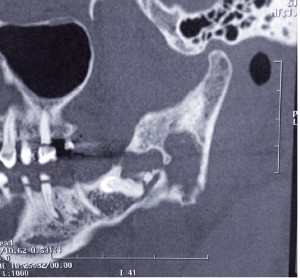

Le TDM retrouve une lésion lytique du ramus mandibulaire avec amincissement des corticales linguale et vestibulaire.